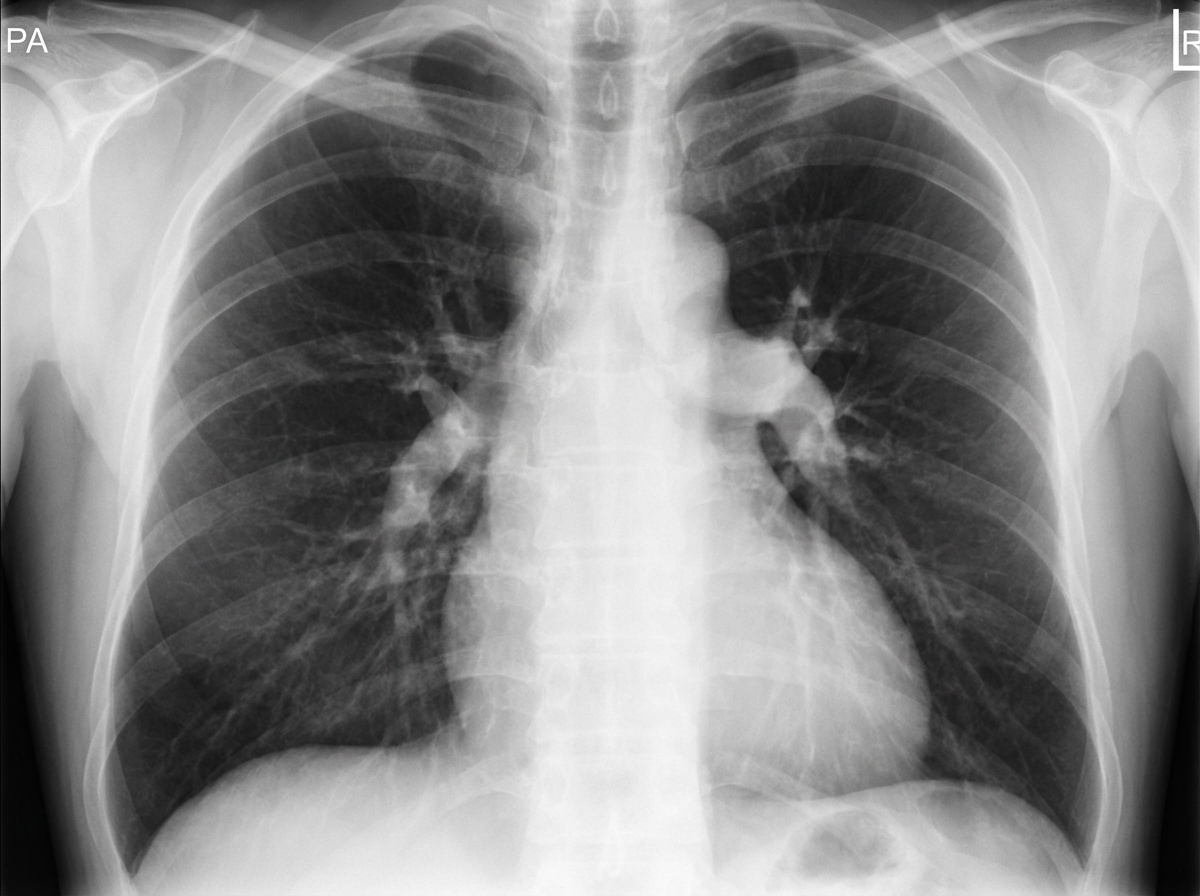

Explanation: ***Pulmonary artery hypertension*** - Classic chest X-ray findings include **enlarged main pulmonary artery** and **right heart enlargement** with prominent right ventricle. - **Peripheral pruning** (oligemia) shows decreased vascular markings in outer lung fields due to elevated pulmonary pressures. *Interstitial lung disease* - Chest X-ray typically shows **reticular opacities** and **honeycombing** in lower zones, not the vascular changes seen here. - Associated with **progressive dyspnea** and **dry cough**, but lacks the cardiac enlargement pattern. *Congestive heart failure* - Presents with **cardiomegaly** and **pulmonary edema** showing **Kerley B lines** and **bat-wing** distribution. - **Bilateral pleural effusions** and **cephalization** of pulmonary vessels are common findings. *Bronchiectasis* - Characteristic **tram-track** and **ring shadows** representing dilated bronchi with thickened walls. - Associated with **recurrent infections** and **productive cough** with purulent sputum, not vascular prominence.